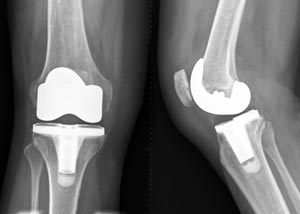

Knee replacement surgery — also known as knee arthroplasty (ARTH-row-plas-tee) — can help relieve pain and restore function in severely diseased knee joints. During knee replacement, a surgeon cuts away damaged bone and cartilage from your thighbone, shinbone and kneecap and replaces it with an artificial joint made of metal alloys, high-grade plastics and polymers.

Knee replacement surgery (arthroplasty) involves replacing a damaged, worn or diseased knee with an artificial joint.